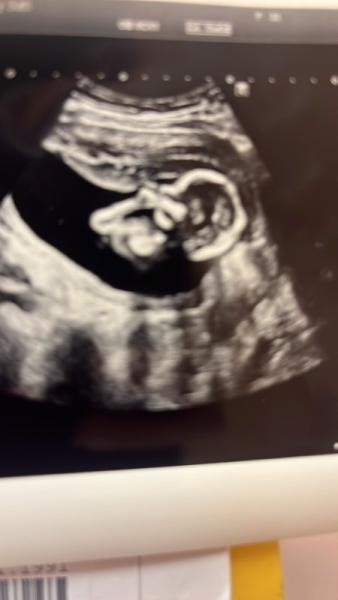

Hallo ihr Lieben! Ich war diese Woche bei 11+0 wieder beim Ultraschall. Meine Freundin hat mir von der Skull Theorie erzählt und jetzt rätseln wir beide. Kennt sich jemand aus? Was würdet ihr tippen? :)) P.S.: Sowohl Mädchen als auch Junge sind natürlich herzlich willkommen. Ich weiß, dass das am Ende nur orakeln ist, aber es macht ja trotzdem Spaß.

Bild zu Skull Theorie: Mädchen oder Junge - Schwanger - wer noch? Rund um die Schwangerschaft

Also meiner Meinung nach sieht man da garnichts, da die Stelle, die man dafür betrachtet total verschwommen ist. Aber selbst wenn man was sehen würde, ist es trotzdem nicht gesagt, dass es dann auch stimmt

Sehe ich genauso … das Bild ist für diese Theorie leider völlig ungeeignet.

Okay...dann ist das Bild zu unscharf? Oder einfach nur die Postion ungeeignet?

Leider ist es dafür nicht klar genug. Bei mir hat die skull theory aber zwei mal gestimmt. Falls du ein besseres Bild hast.

Ich habe leider kein anderes Bild...erst wieder beim nächsten Ultraschall. Das Gerät von meinem Arzt ist wohl nicht das allerbeste....